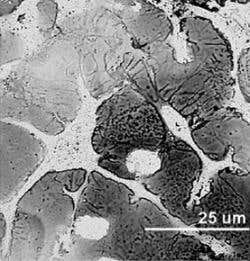

Soaking brain cells in a polymer solution that sets like rubber around them could provide a better connection for future brain implants – here the polymer shows the impressions of cells it has formed around (Image: Institute of Physics)

Running a small current through the wires caused the monomers to form rubbery conductive polymer in a close-fitting web around the cells.

“It forms a network in the tiny gaps between cells,” Richardson-Burns explains, “we think that will allow a better long-term connection.”

Electron microscope images suggest that even plain PEDOT interacts in some way with the framework known as the extracellular matrix that naturally surrounds cells.